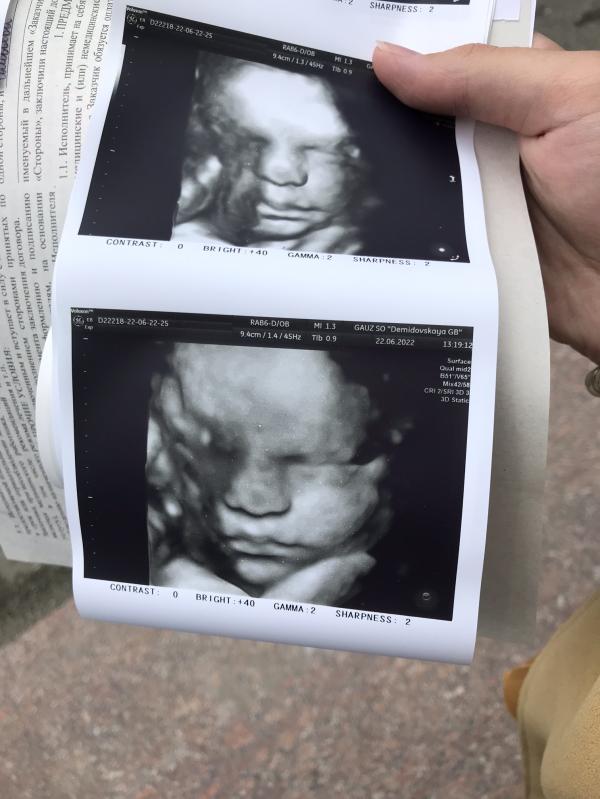

Вчера ходили с мужем на 4-д узи, божечки, это тааак волнительно 🥰

Сказали, что у нас ооочень серьёзный парень)))

Только под конец узи удостоил нас своей улыбкой😄